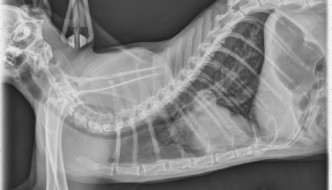

12 year old DSH

Today's case is a 12 year old male neutered Domestic Shorthair with episodes of coughing and open mouth breathing. What are your findings? … [Read more...]